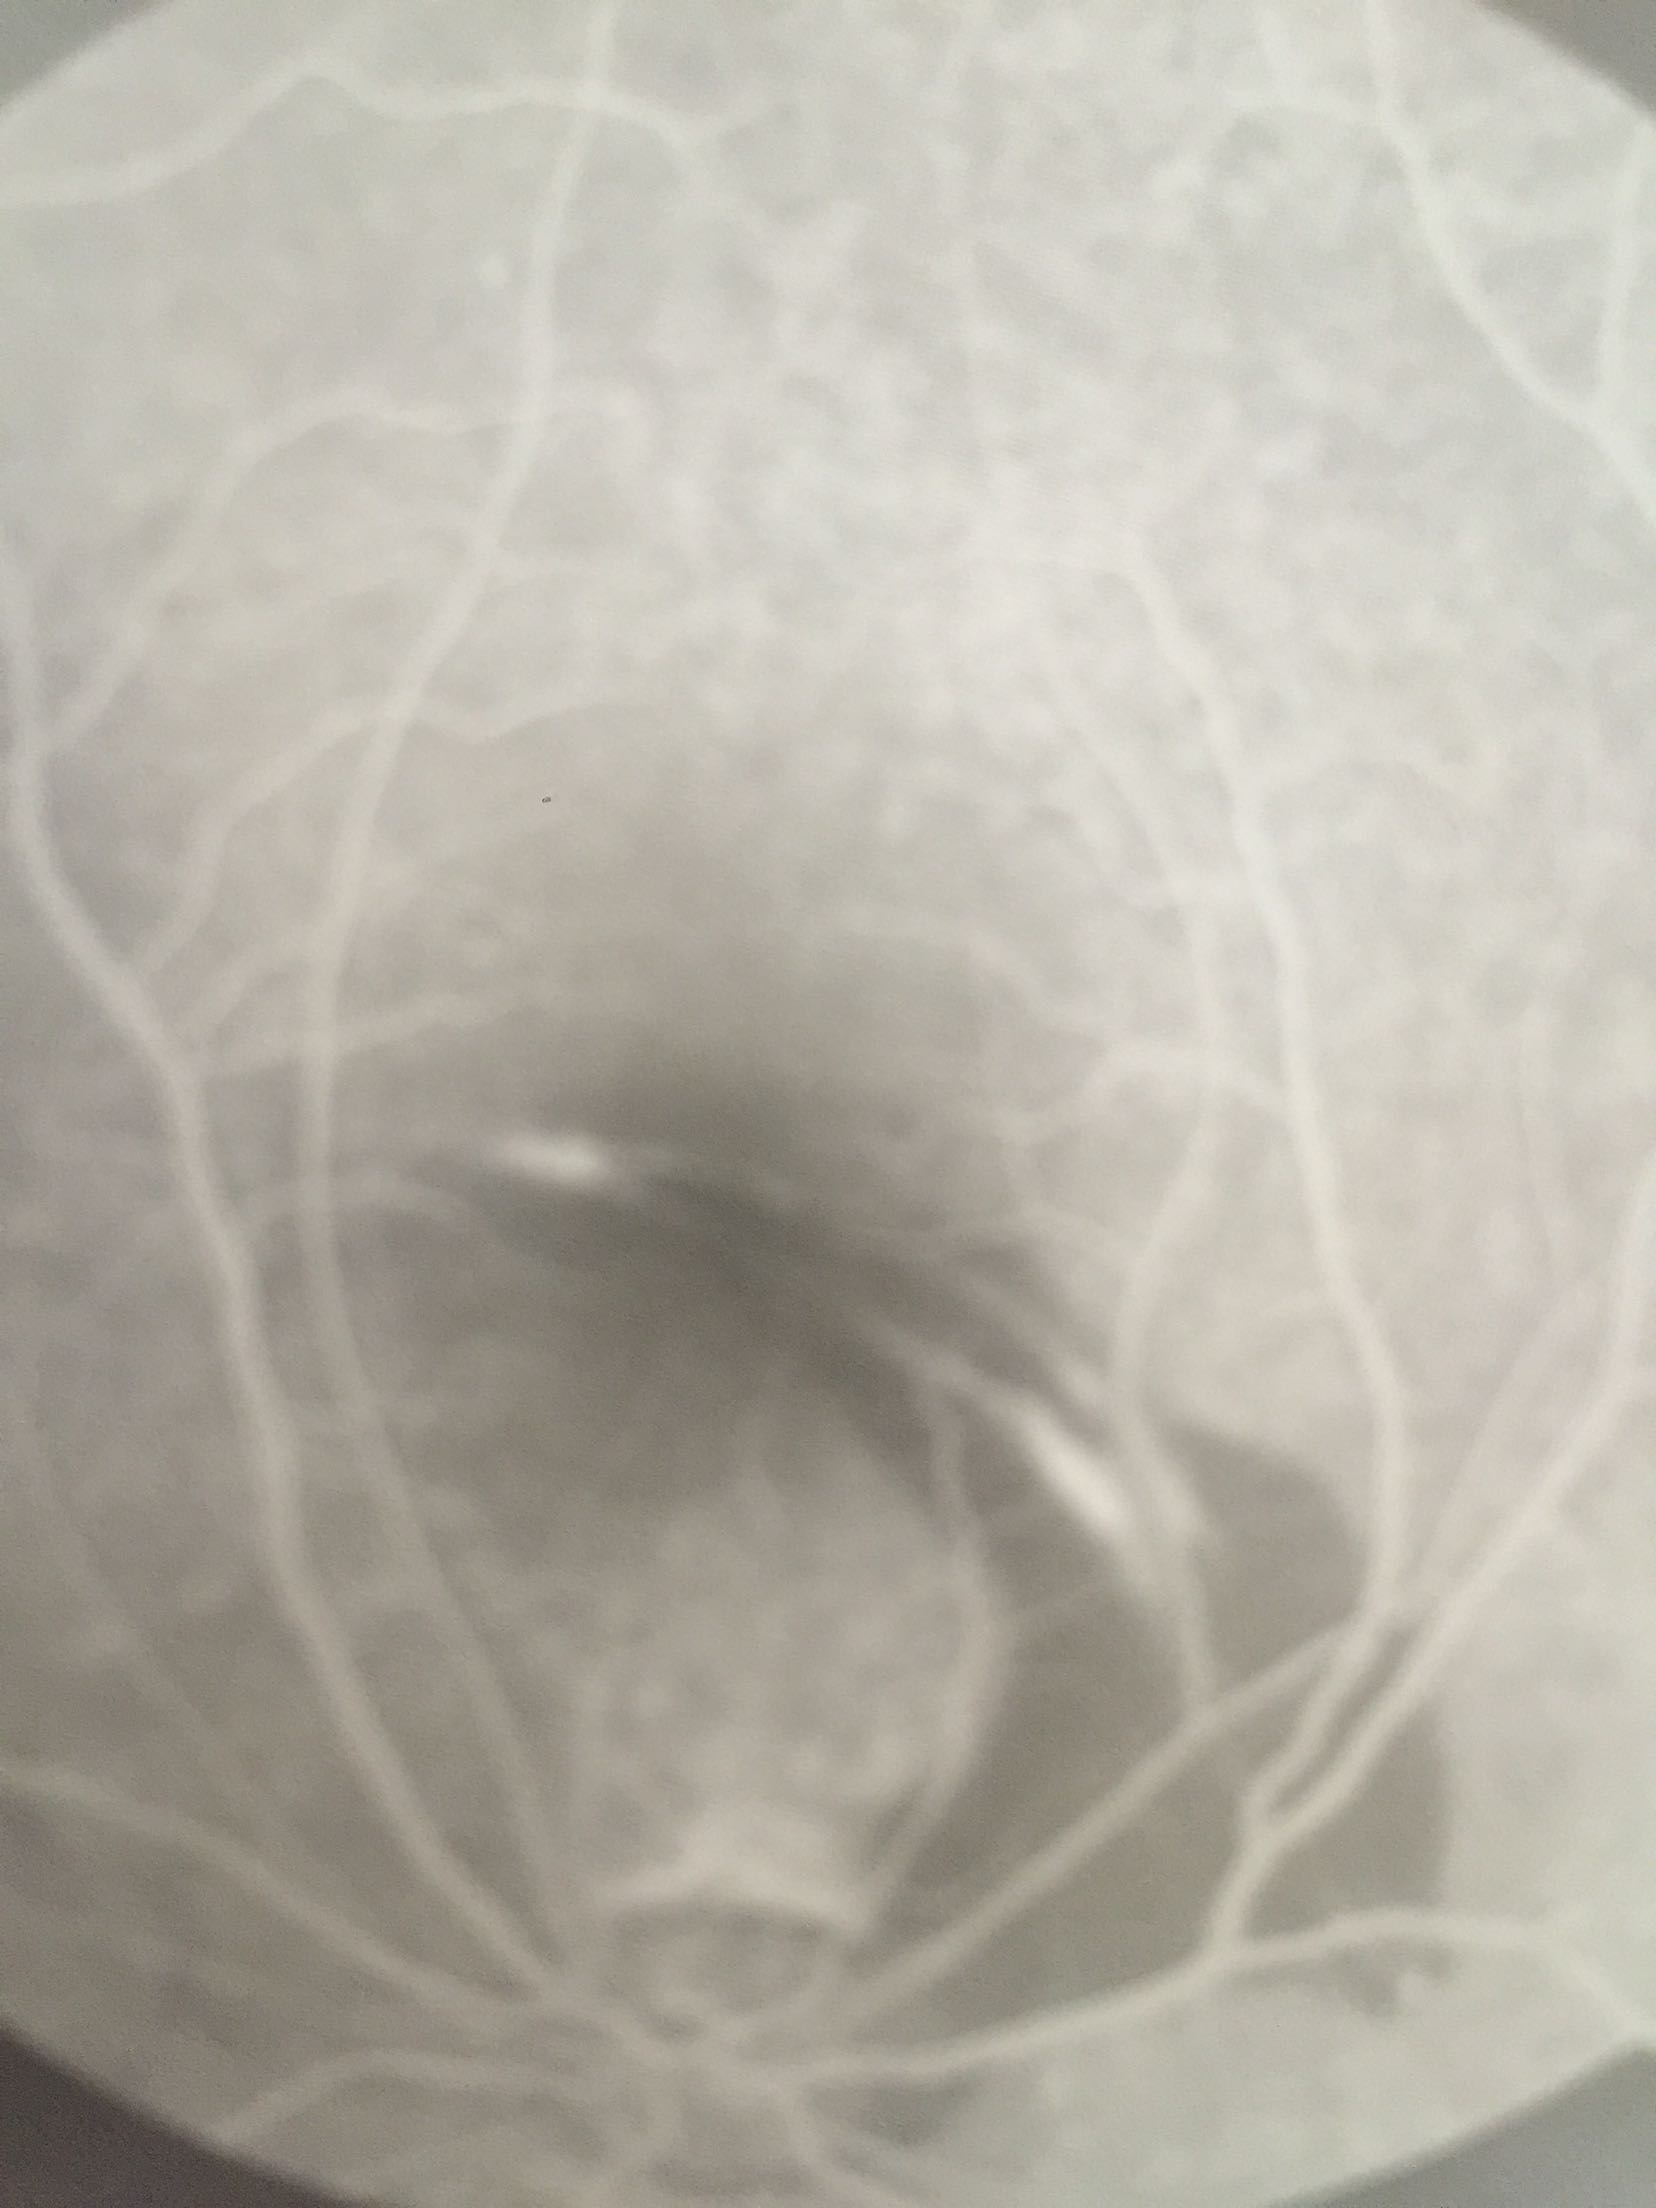

视力:右眼 0.2不能矫正 左眼1.0 眼压:16/19mmhg右眼结膜充血+角膜透明,前房3.0CT。晶体玻璃体透明。眼底视盘界清色可,颞上方血管弓与黄斑区之间可见一弧形脉络膜裂伤,裂伤处及其周围视网膜下可见浓厚出血。